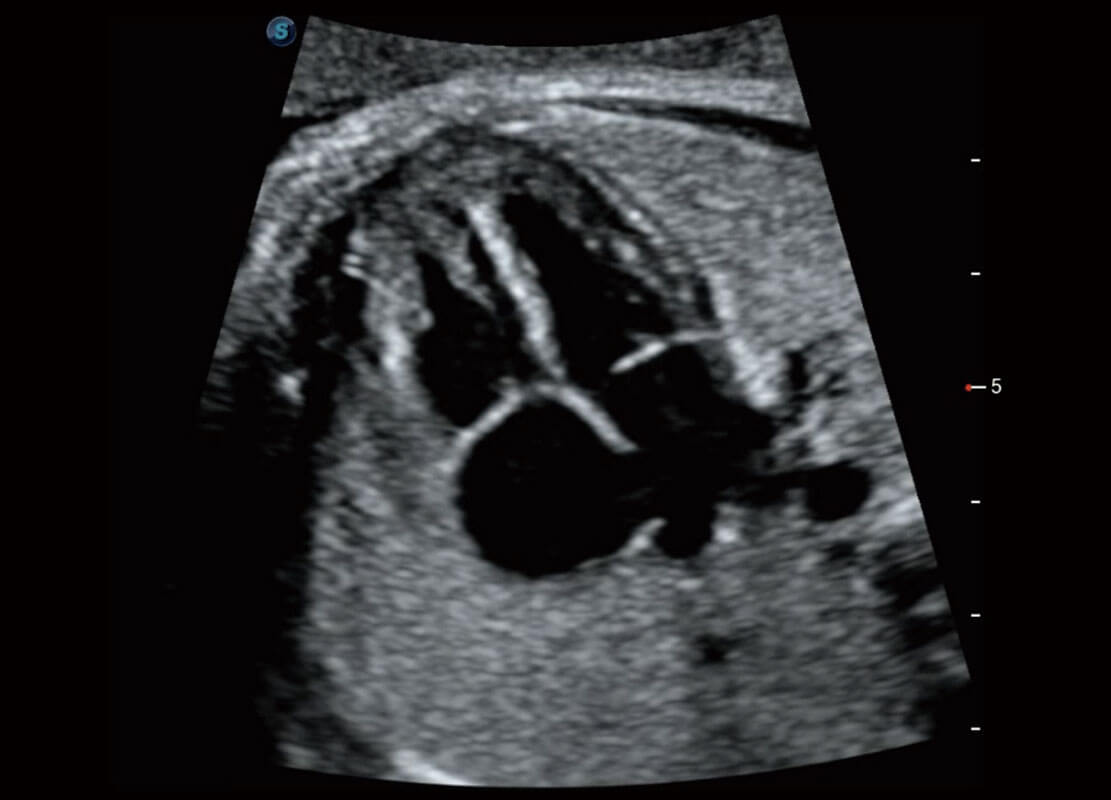

P60優(yōu)異的圖像質(zhì)量搭載專科探頭,在婦科基礎(chǔ)疾病的診斷、卵泡生長(zhǎng)的監(jiān)測(cè)、輸卵管通暢情況的判別等方面為您提供生殖應(yīng)用方案。

腔內(nèi)三維-光影成像